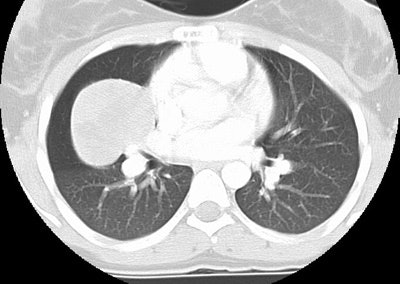

CT lung windows reveals the mass to lie along the minor fissure- this was confirmed at surgery: